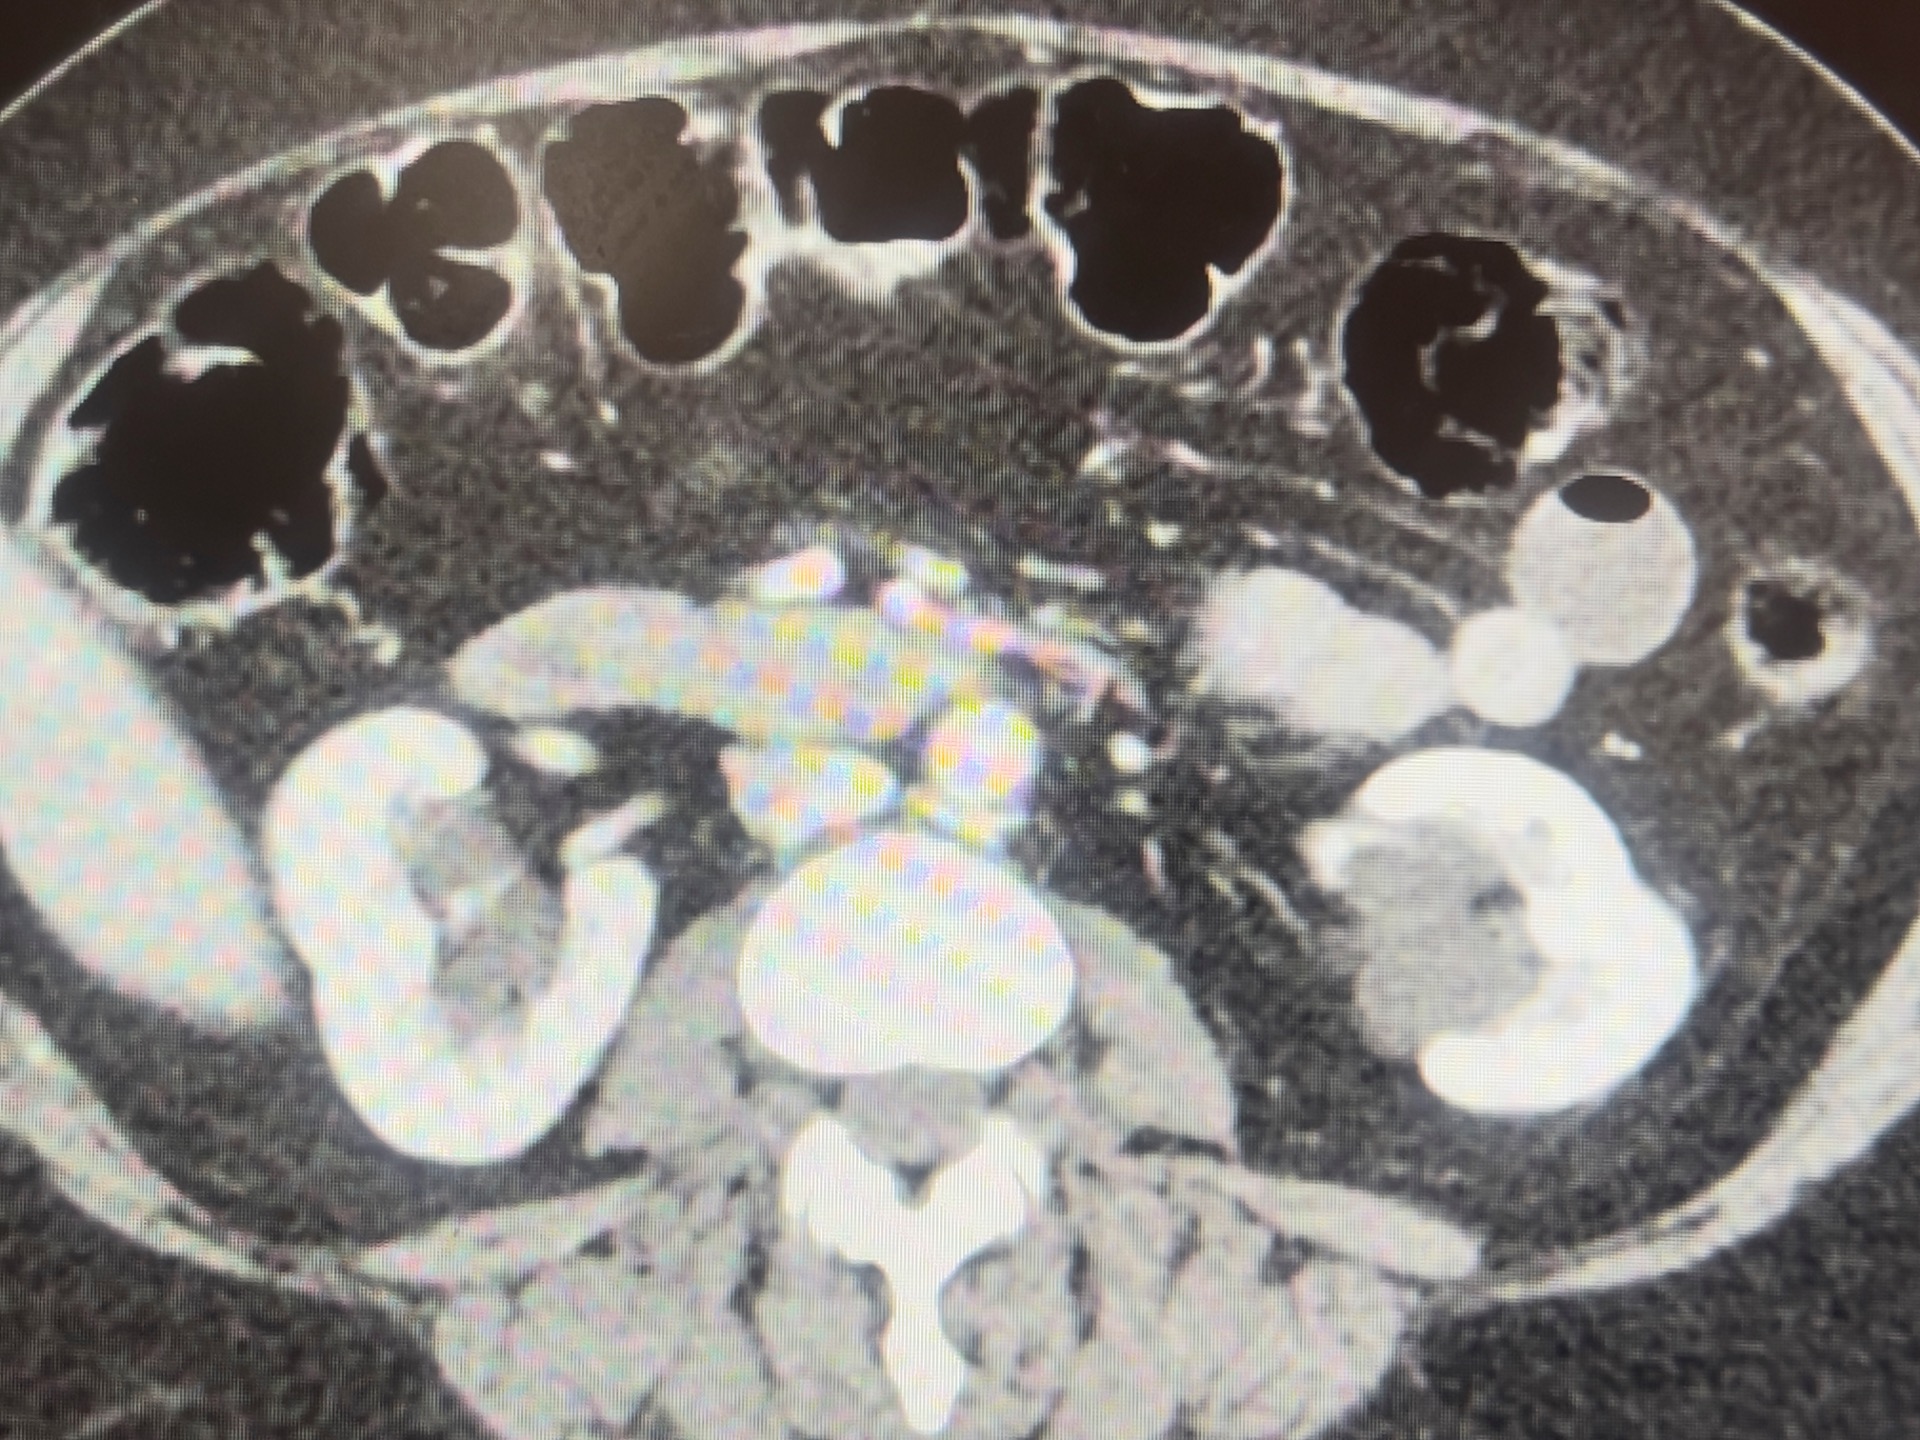

CT revealed that what appeared as hydronephrosis on US was actually bilateral parapelvic cysts.

Parapelvic cysts are benign and unrelated to ureteric obstruction. They do not communicate with the collecting system and are thought to be lymphatic in origin. However, there have been case reports of cysts causing obstructive Sx due compression of the renal pelvis (1).

However, importantly, it is one of the causes of an erroneous diagnosis of hydronephrosis on US. Important features to help you differentiate are:

If you look closely at her US images, you can see that her cortex is normal thickness bilateral despite quite significant "hydronephrosis". Also on the left, the anechoic areas seem discrete and round.